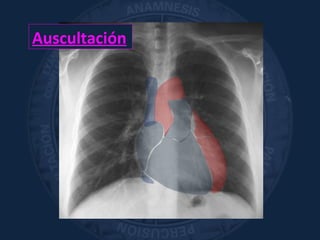

Auscultación

«apreciación con el sentido del

oído de los fenómenos acústicos

que se originan en el organismo»

Laënne

Sist. Circulatorio

Sonidos cardíacos normales, soplos, sonidos agregados.

CARÓTIDAS. Art. RENALES

Pulmón y Vía Aérea

Ventilación alveolar, alteraciones en el flujo aéreo,

sonidos agregados

Abdomen

Ruidos hidroaéreos/Borborigmos